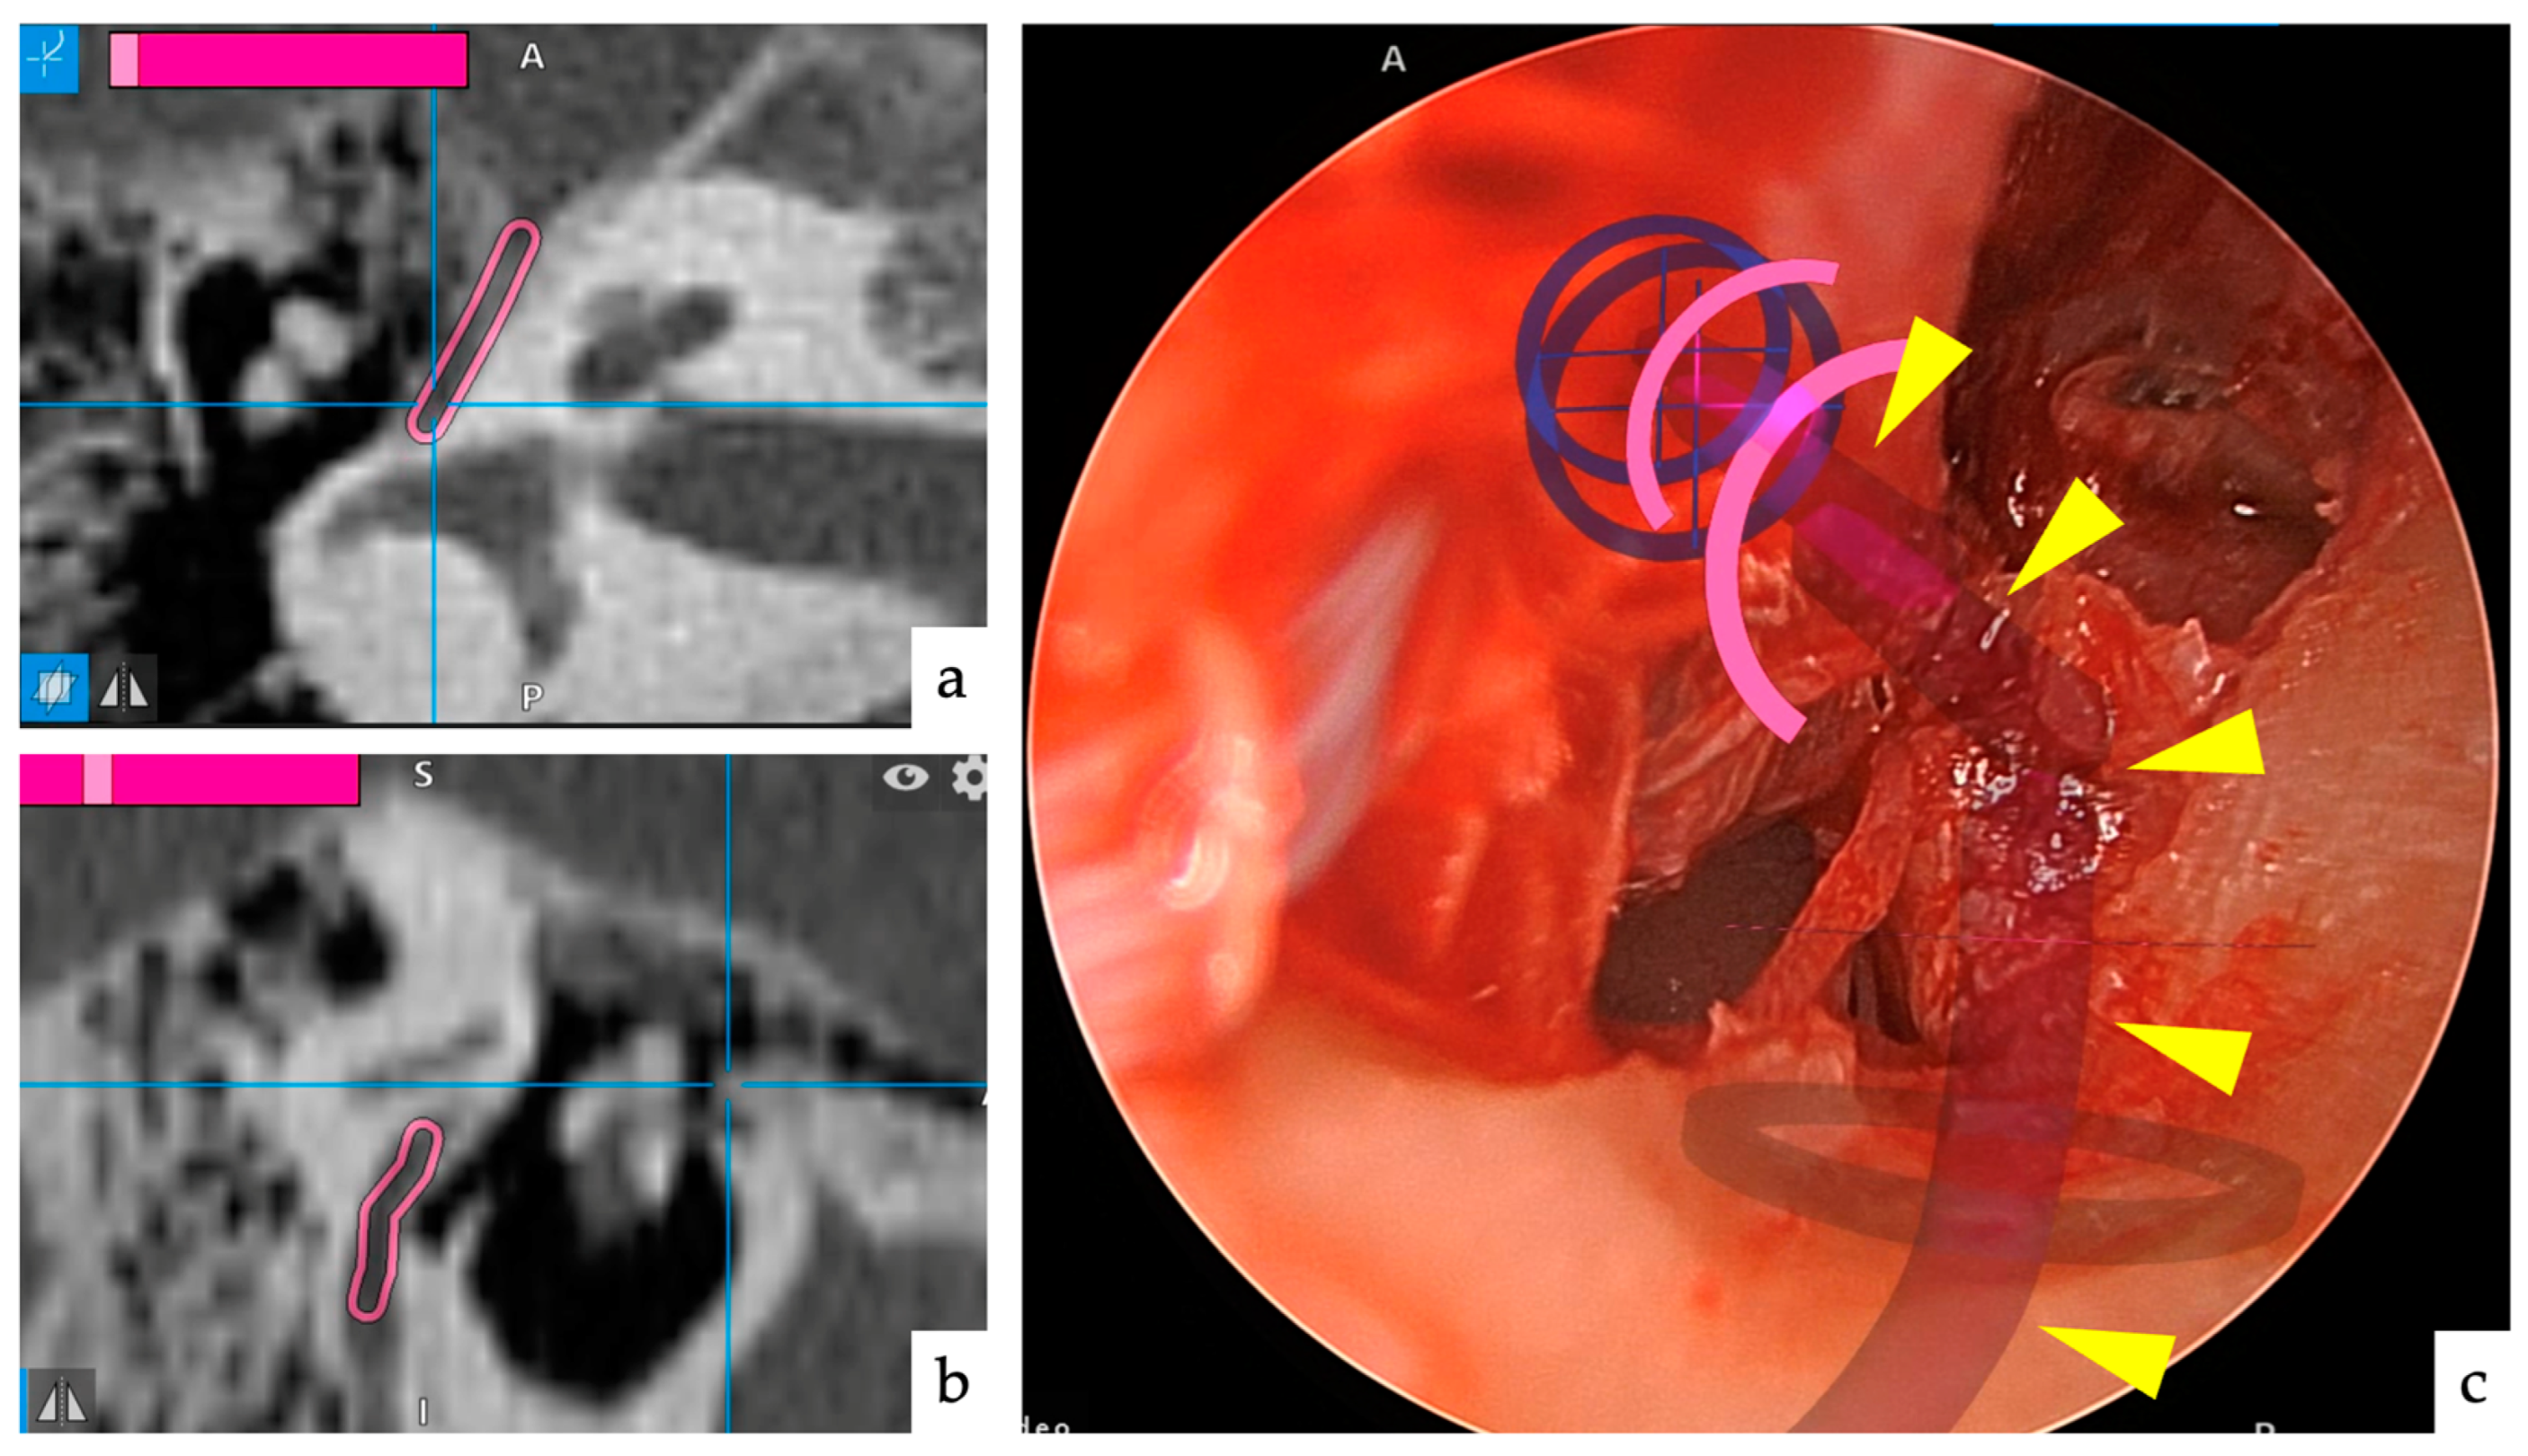

| Case | Age | Sex | Type | Range | TEES/MES |

|---|---|---|---|---|---|

| 1 | 44 | Male | pars flaccida | AM | TEES |

| 2 | 51 | Female | pars flaccida | TAM | MES |

| 3 | 41 | Male | pars flaccida | AM | TEES |

| 4 | 5 | Female | congenital | TAM | TEES |

| 5 | 41 | Male | pars flaccida | AM | TEES |